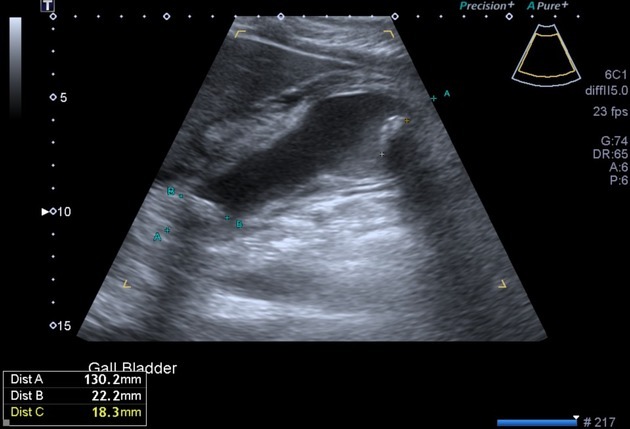

what is tumefactive sludge?

sludge balls

thick sludge that mimics an GB mass

ultrasound appearance of sludge balls

avascular mass with low-level echoes